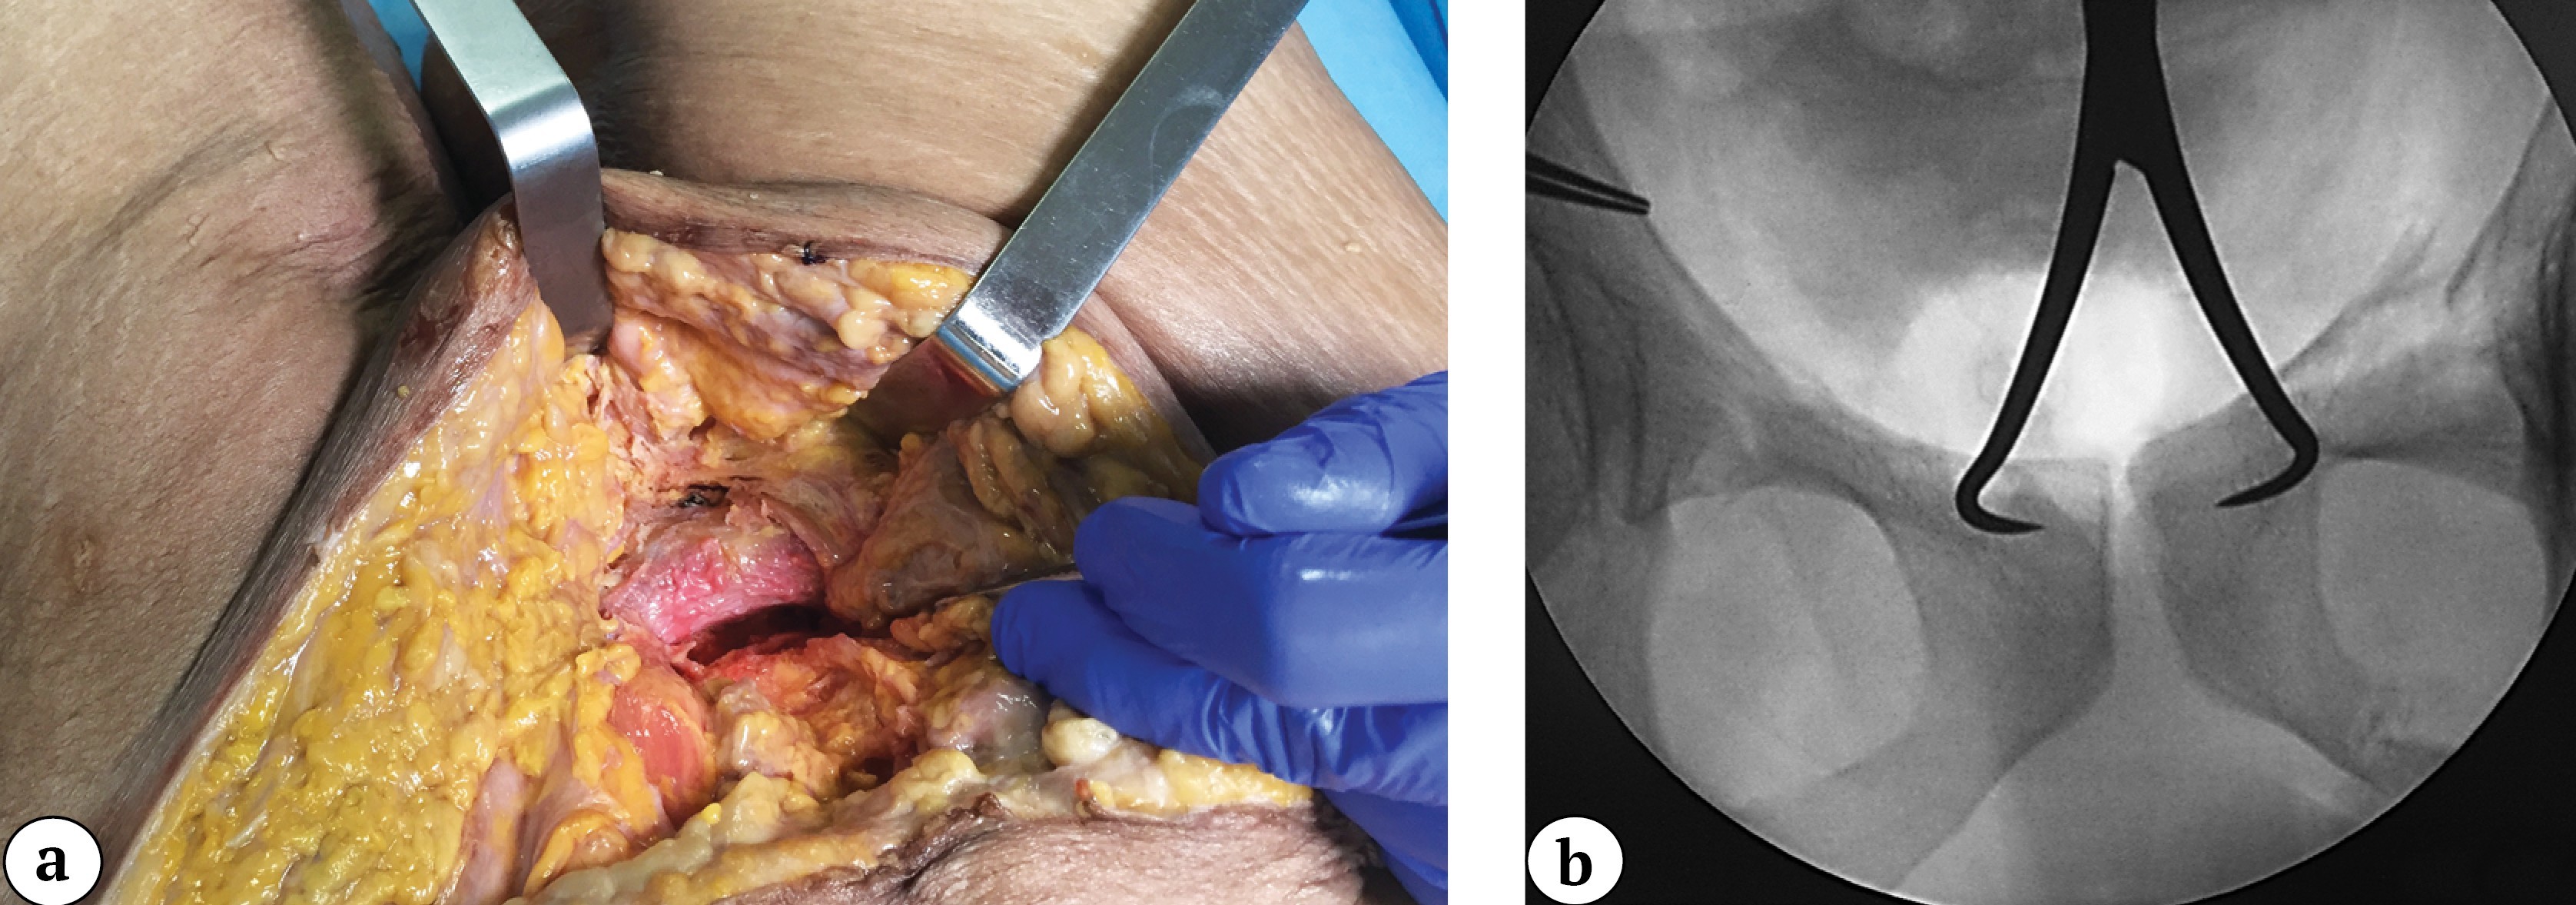

If necessary, the nail was slightly adjusted in a retrograde or antegrade direction to achieve precise alignment of the drill sleeve with the plate hole. The nail was then locked with two 3.5-mm cortical screws through the plate holes (Figure 5). The guide was removed and attached to the second nail (the ends of the nails usually protrude 1-2 mm from the entry points and are easily palpable). The optimal angle of the guide for subsequent nail locking was achieved by rotating it around the nail axis under C-arm control.

Figure 5. Intraoperative obturator-outlet view of the pelvis during locking of the nail with a 3.5-mm screw through the plate hole (a); intraoperative photograph of the surgical site showing interlocking of the second nail through the plate hole (b)

Standard positioning of the plate after osteosynthesis and the view of the surgical field prior to closure are shown below (Figure 6).

Figure 6. Intraoperative anteroposterior view of the pelvis after combined fixation with the nail-plate system (a); intraoperative photograph of the surgical site prior to wound closure (b)